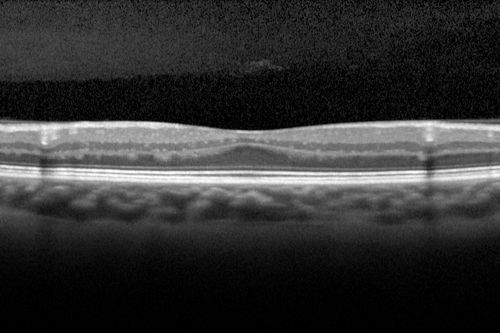

Foveal hypoplasia - aplasia

SD OCT shows persistent plexiform layers in the center of the macula